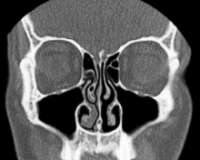

Говорили что кривая, но допустимо. Исправлять ХЗ, есть смысл если боксирую ?

Насчёт зубов, может на снимках видно... Мне об этом ничего не говорили, сам не отдупляю в снимке.

Первый полгода назад до синусита, второй недели 3 назад делал в расцвете синусита, когда нос еле дышал. Второй снимок, это не у меня руки кривые, он сам мутный такой.

На твоих снимках не самая страшная картина, разве что вуаль в левой лобной пазухе, по фотке сложно сказать.

Наиболее иеформативное исследование - КТ придаточных пазух носа, но в твоем случае вроде не нужно. КТ делают, если подозрение на кисты, инорогдные тела или синусит какой-то злой.